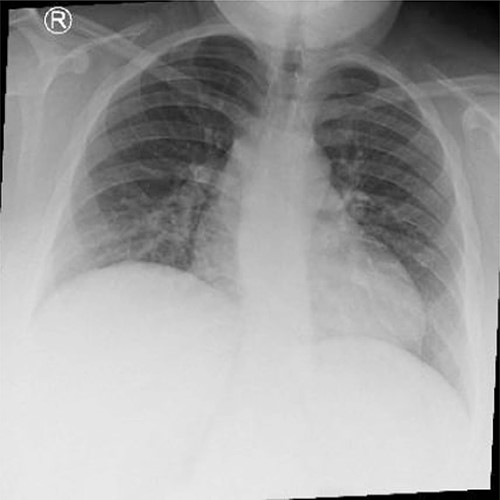

The patient underwent complete preoperative workup which includes clinical history, physical examination, complete blood count (CBC), coagulation profile, chemistry, lipid profile, endocrinology tests, US abdomen, chest X-ray, transthoracic echocardiography, computed tomography (CT) chest and CT abdomen, which showed reversal of intra-abdominal organs as shown in Figs 1, 2 and 3.